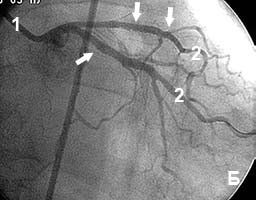

Пациент с жалобами на боли в сердце в покое (нестабильная стенокардия). В анамнезе - инфаркт миокарда.

На коронарограмме (рис 6а) - множественные стенозы ветвей левой коронарной артерии.

В место стенозов установлены коронарные стенты. Стенозы полностью устранены (рис.6б)..

Сразу же после вмешательства приступы болей прекратились.

Рис.6 Множественные стенозы ветвей левой коронарной артерии до (А) и после (Б) стентирования.

1 - катетер; 2 - контрастированные артериальные ветви; стрелками отмечены зоны стенозов. |